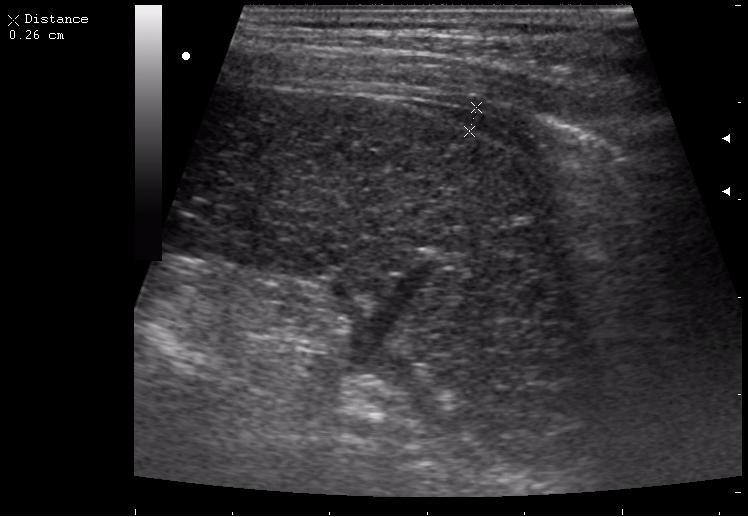

>желтой стрелкой - это левый надпочечник?

Похоже.

Он обычно располагается больше кнутри от верхнего полюса почки и может досигать ее ворот.

Надежнее визуализировать ЛН из позиции, которую я показывал в известной Вам теме.